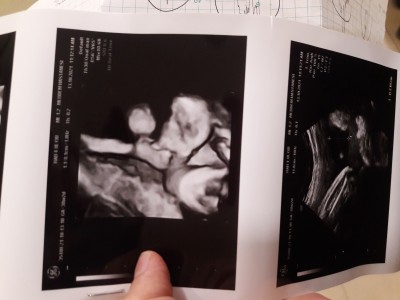

Ay kizlar devletle ozel nasilda farkediyor.ilk defa ozele gittim verdigi ultrasona bakin nasılda net yuzu. Devlette hep siyah kagit vermislerdi bana. Bunu görünce cok mutlu oldum ilk defa boyle net gordum yuzunu :angel:<3 38+2 doktor suyun azalmaya başlamış %60 a düşmüş. Sancilarda başlamış suan hissetmiyorsun ama başlamış dedi. 2 gun sonraya birdaha cagirdi . Fotoya yan çevirip bakin ters yuklenmis çünkü :d

Özelde ki doktor iyiyse bazen renkli bile gösteriyor ♥️ sağ salim kucağına alırsın inşallah

Birisi tupulu tv, digeri lcd :D